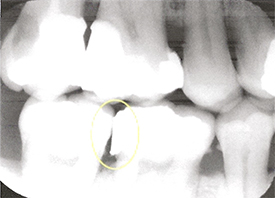

Overhangs cause dental problems When a restoration is too bulky in the area where the restoration meets the tooth, we call it an overhang. In contrast, with an ideal restoration, there is a seamless t....